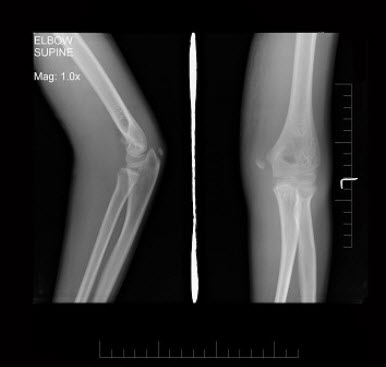

261、单项选择题

男,11岁,左肘外伤,根据所示图像,最可能的诊断是()

A.左肱骨内上髁骨骺Ⅰ度分离

B.左肱骨内上髁骨骺Ⅱ度分离

C.左肱骨内上髁骨骺Ⅲ度分离

D.左肱骨内上髁骨骺Ⅳ度分离

E.左肱骨内上髁骨骺Ⅴ度分离